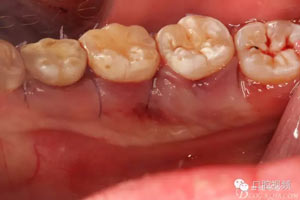

圖11.清理拔牙創(chuàng)。

圖13.縫合,舌側(cè)組織輕度反應(yīng)